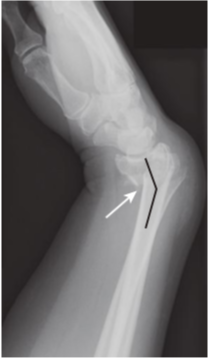

Nutrient canal versus fracture.

Fracture lines, when viewed in the correct orientation, tend to be “blacker”(more lucent) than other lines normally found in bones, such as nutrient canals. A,This is a nutrient canal (white arrows), whereas a true fracture is seen in another patient in (B)(dotted black arrows). Notice how the nutrient canal has a sclerotic (whiter) margin and is confined to the cortex, which is not the case with fracture lines that are darker and traverse the cortex and medullary cavity. The edges of a fracture tend to be jagged and rough.